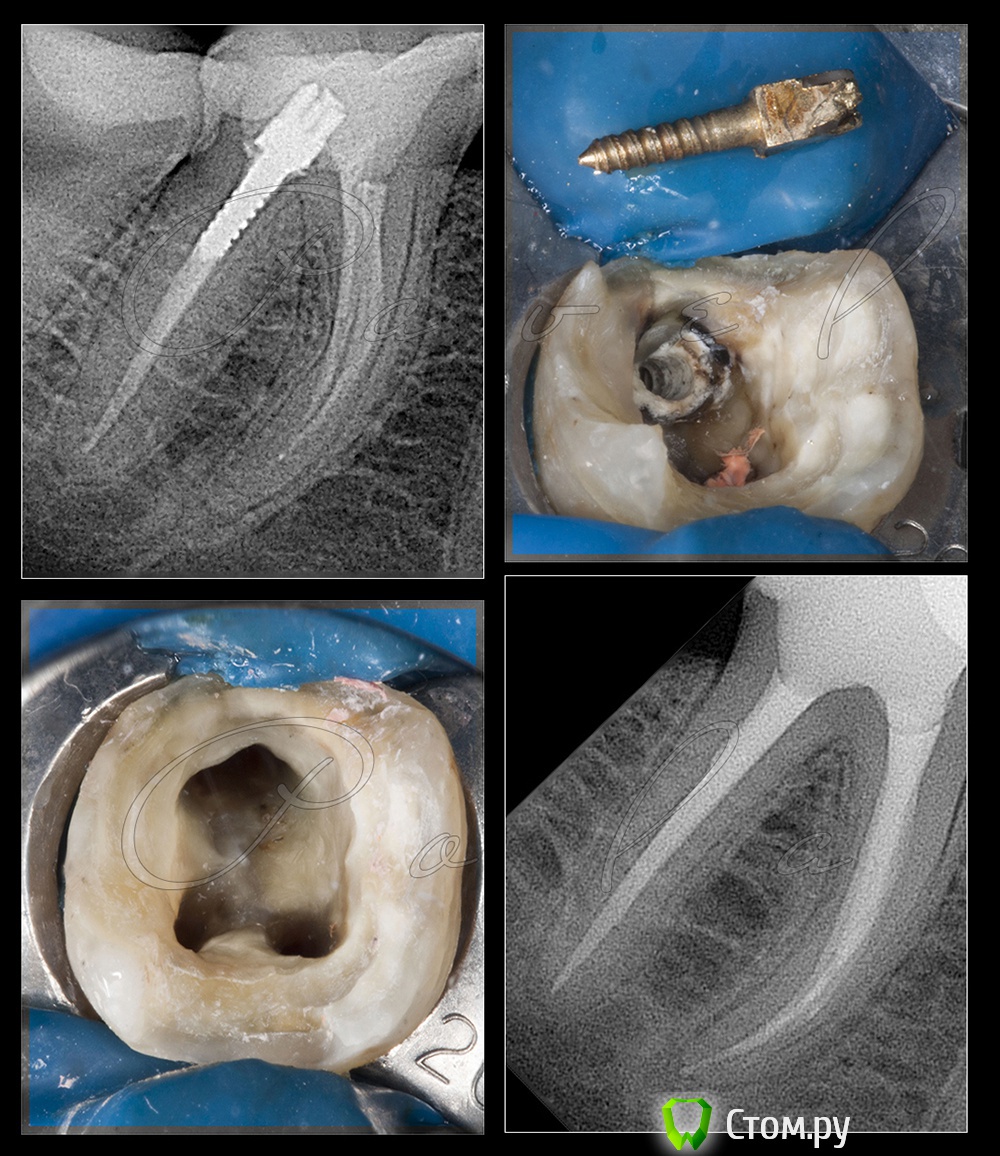

M@estro Опубликовано 17 июня, 2014 Поделиться Опубликовано 17 июня, 2014 (изменено) http://i017.radikal.ru/1406/ba/4b4d32624cce.jpg http://s020.radikal.ru/i715/1406/2c/13037b79cbc1.jpg http://s019.radikal.ru/i608/1406/42/9531a2f4ac7a.jpg http://s018.radikal.ru/i520/1406/1f/9a76c0d6d933.jpg Описать - то забыл Зуб 1.7 ,жалобы на скол. Изменено 17 июня, 2014 пользователем M@estro 12 Ссылка на комментарий

M@estro Опубликовано 17 июня, 2014 Поделиться Опубликовано 17 июня, 2014 Техничка звонит и говорит -"доктор,будет ступенька в области уступа,т.к. нельзя делать имакс тоньше 1 мм " (с) Пришлось вину на себя брать ; ) Специально фоту с эмалью выложил, как думаете,хрупнет? Ваши ставки,господа Ссылка на комментарий

DmitrySH Опубликовано 18 июня, 2014 Поделиться Опубликовано 18 июня, 2014 Техничка звонит и говорит -"доктор,будет ступенька в области уступа,т.к. нельзя делать имакс тоньше 1 мм " (с) Пришлось вину на себя брать ; ) Тоже периодически звонят на такие темы Это они про оральный или вестибулярный уступ? По жевательной какая толщина? Ссылка на комментарий

M@estro Опубликовано 18 июня, 2014 Поделиться Опубликовано 18 июня, 2014 Тоже периодически звонят на такие темы Это они про оральный или вестибулярный уступ? По жевательной какая толщина? ПО жеватке там 1 - 1.5 . Про вестибулярный уступ Я их не виню, хорошо что позвонили хоть, а не "на готово" сделали . Их понять - то можно, народ что только не делает - и на временный фиксируют имакс, и на фуджик, что при такой толщине критично, конечно. Неа, не хрупнет Можно сказать,что это был риторический вопрос 1 Ссылка на комментарий